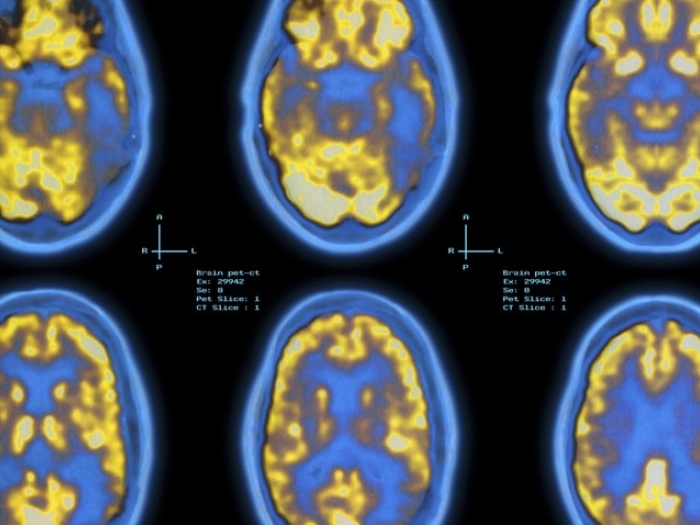

‘Game-Changing’ Alzheimer’s Drug Just a First Step

U-M neurologist shares her thoughts on new Alzheimer's Disease treatment, aducanumab. Learn why she is tempering expectations for the new Alzheimer's treatment.